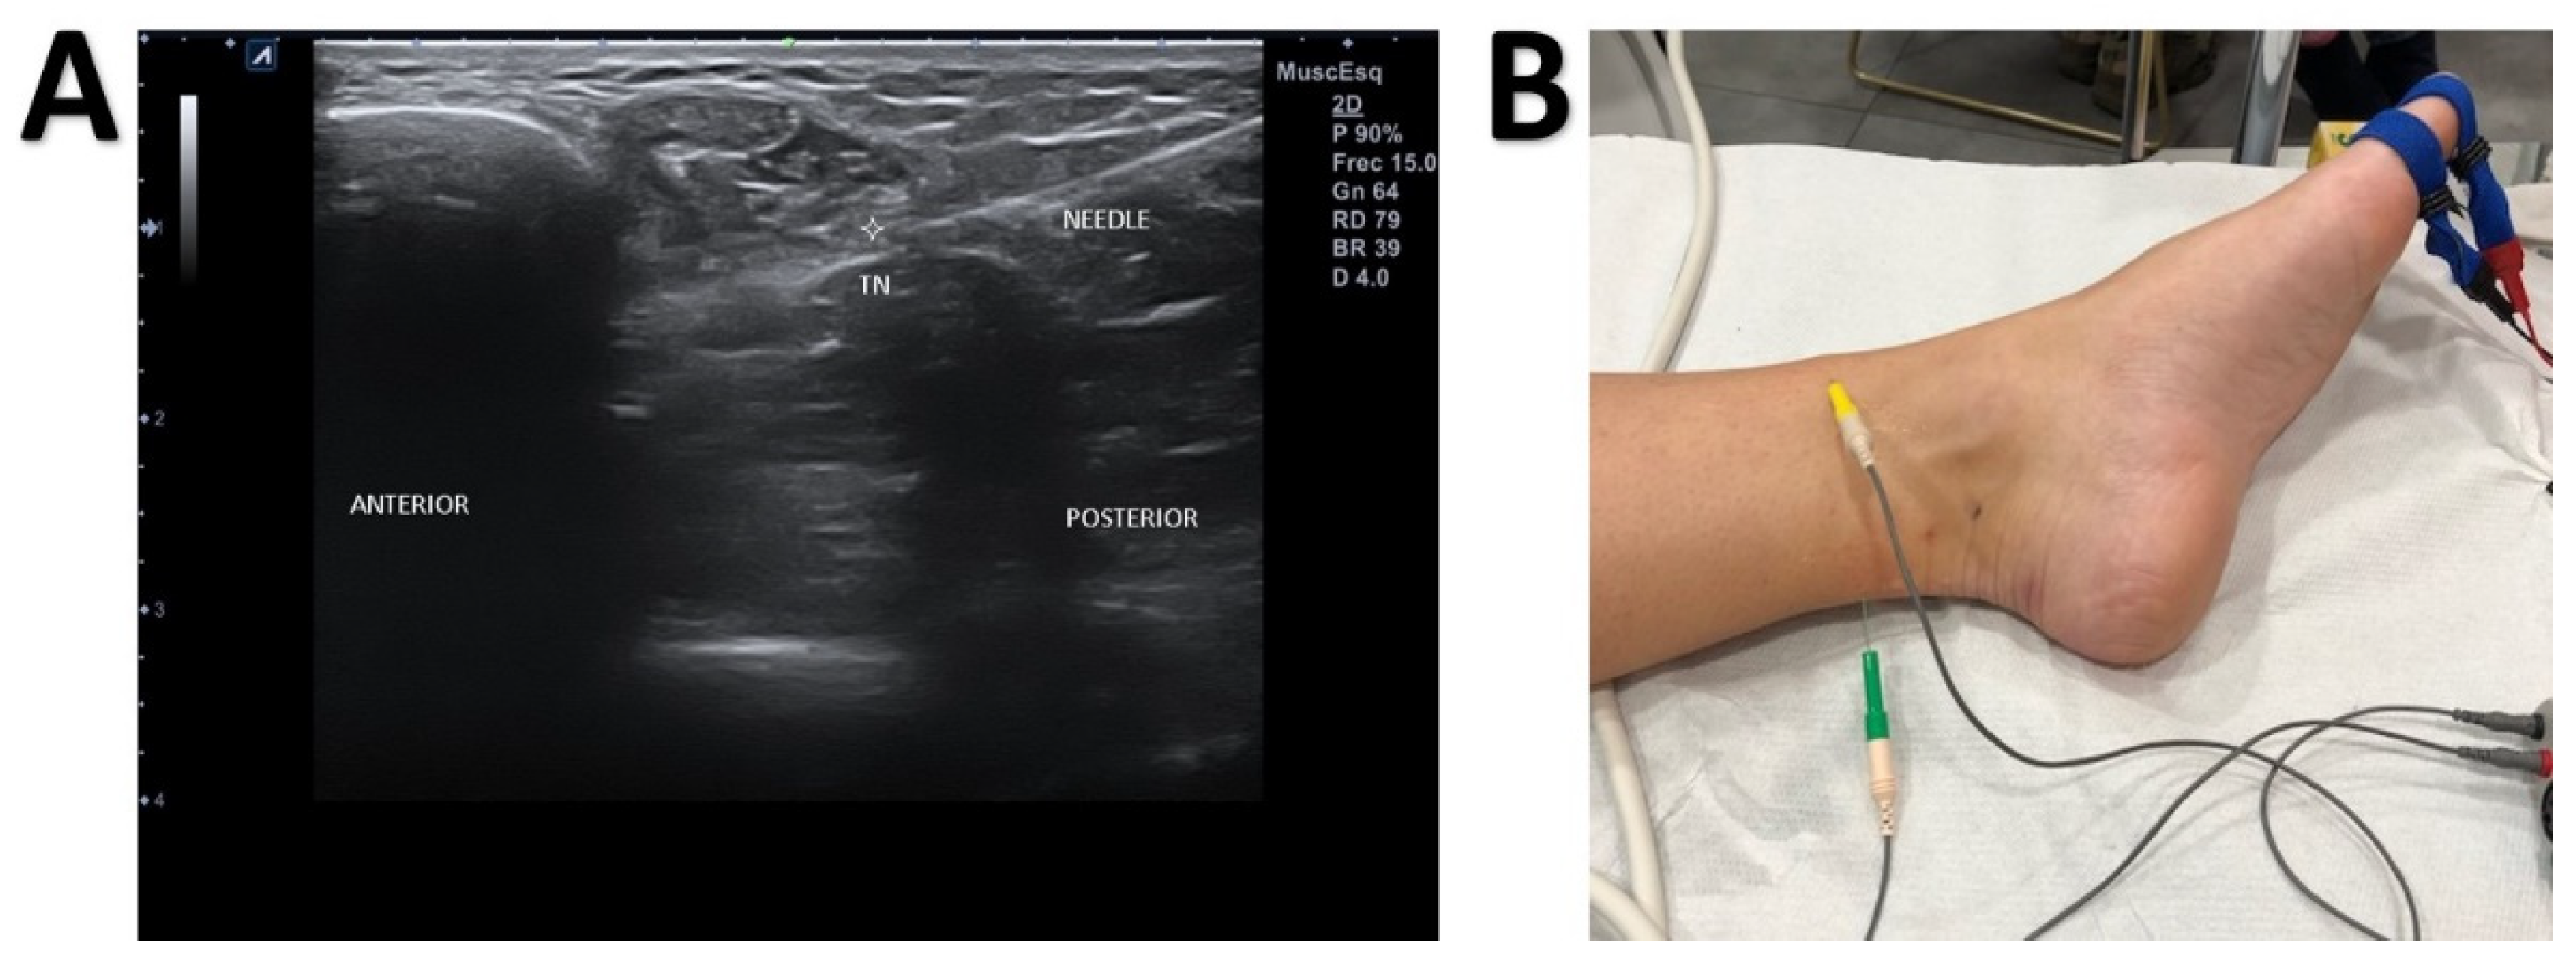

JCM Free FullText UltrasoundGuided NearNerve Needle Sensory Baxter's Nerve Block It is an entrapment syndrome, like carpal tunnel syndrome in your hand. baxter’s entrapment is an entrapment (or compression) of the inferior calcaneal nerve just under the base of the arch of the foot. the first branch of the lateral plantar nerve (fblpn), also known as inferior calcaneal nerve or, more commonly, as. baxter neuropathy is a. Baxter's Nerve Block.

JCM Free FullText UltrasoundGuided NearNerve Needle Sensory Baxter's Nerve Block baxter nerve entrapment and tarsal tunnel syndrome. It is an entrapment syndrome, like carpal tunnel syndrome in your hand. This is an entrapment of a nerve in. the first branch of the lateral plantar nerve (fblpn), also known as inferior calcaneal nerve or, more commonly, as. Tarsal tunnel syndrome is characterized by an entrapment of the. baxter. Baxter's Nerve Block.